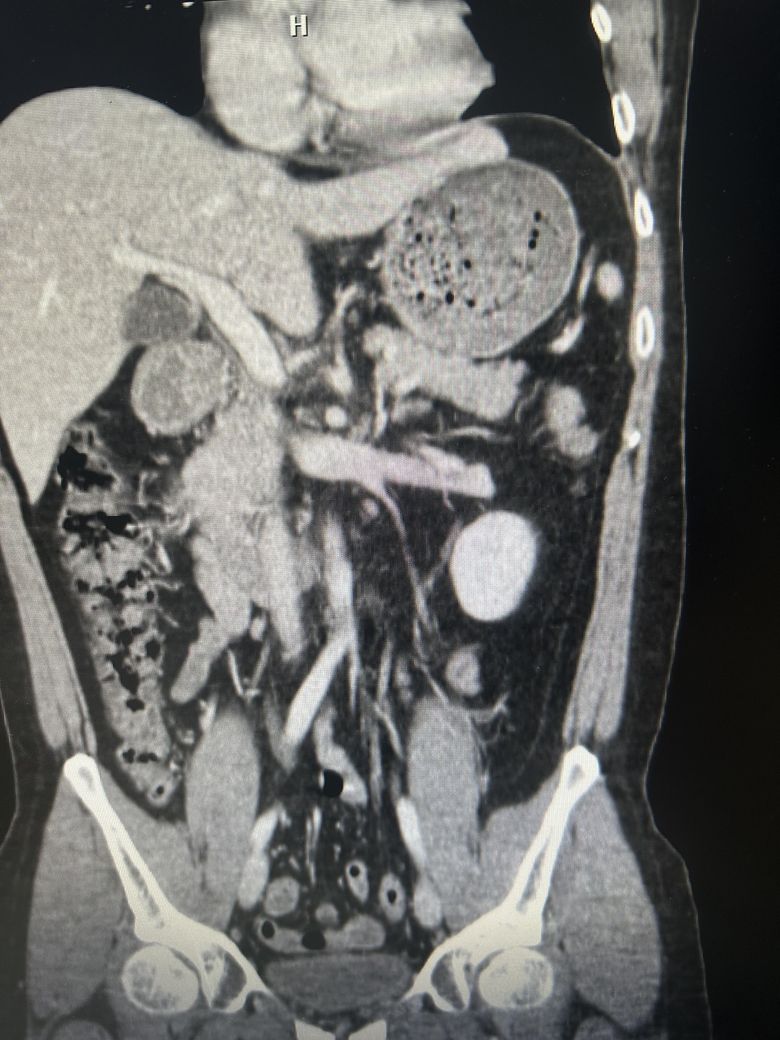

담낭염일 까요?? (CT 사진 있어요)

우상복부 통증(좌상복부 통증도 생김), 오른쪽 어깨에서 허리까지통증, 소화불량, 팽만감,답답함, 설사 증상이 있는데..... 담낭염이 맞을까요?

• 2번 째 사진

CT에서 담낭염은 담낭벽이 두꺼워보이고 벽이 조영증강되는데

환자분 자료의 경우 그런 소견이 뚜렷하게 보이지는 않는 것 같습니다.

• 애매합니다. 담낭의 크기가 다소 늘어나 보이긴 합니다만, 당남염을 강력하게 의심할만한 다른 소견들이 보이지는 않습니다. 가령 담낭의 벽이 두꺼워지거나 담낭 주변의 염증 소견, 담낭 목을 막고 있는 담석 등이 따로 관찰되거나 하지는 않기 때문에 담낭염을 강력하게 의심하기는 어려워 보입니다. 우상복부의 압통 및 머피징후 등의 신체검진 소견이 있다면 담낭염의 가능성을 고려해볼 수 있겠습니다만, 해당 CT 소견만으로는 판단하기 어렵습니다.

첨부해주신 CT 영상에는 담낭 주변에 두드러지는 염증소견이 관찰되지 않습니다. 다만 영상의 모든 단면을 확인한 것이 아니라서 담석증의 여부에 대해서는 확답드릴 수 없습니다. 증상이 지속되면 내과에서 진료를 받아보시는 것을 권해드립니다.